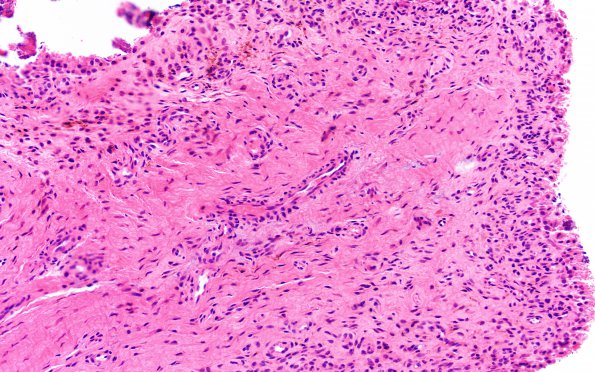

5A2 Synovial Cyst with Hyperplasia (Case 5) H&E 3 A

This specimen represents a synovial cyst with hyperplasia. (H&E)